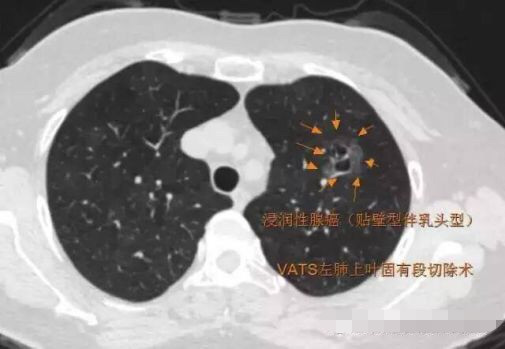

病例4

2013年发现, 每年随访,随访至2016年,病灶逐步增大,2013年5毫米大小,2016年11毫米,3年生长6毫米,平均每年2毫米